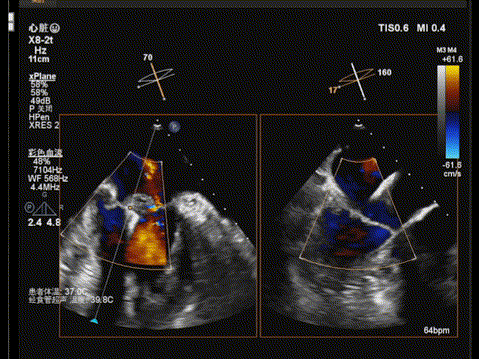

但由于后叶脱垂宽度较大,第一枚夹子释放后活动度较大,为稳定第一枚瓣膜夹并进一步减少反流,遂决定植入第二枚瓣膜夹(长窄型号),第二枚瓣膜夹释放后,经超声心动图评估,两枚瓣膜夹均位置和功能良好,瓣膜夹活动度低,反流进一步减少,平均跨瓣压差为4mmHg,手术顺利完成。

TEE显示,第二枚二尖瓣夹植入后反流进一步减少

TEE显示,平均跨瓣压差为4mmHg